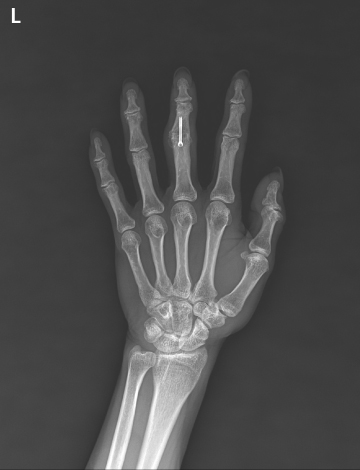

수술후

2022.01.07